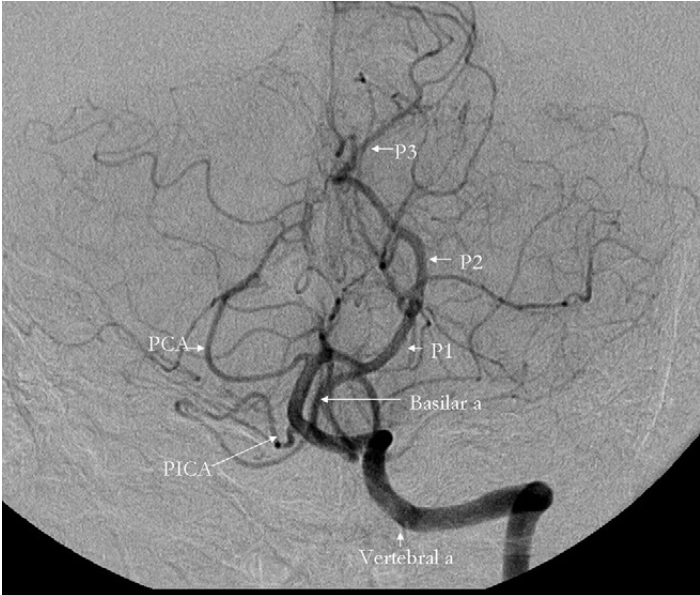

EQUIPMENT: 9 Fr sheath, 8 French BMX 96/Zoom 88 (guide catheter), 6 French Sophia (intermediate/aspiration catheter), marksman 160 CM (microcatheter), Synchro2 soft 014/Aristotle 018 (microwire), 6 mm x 40 mm/ 4mm x 40 mm/ 3 mm x 40 mm Solitaire (mechanical thrombectomy device), 8Fr/6 Fr Angioseal (vascular closure device), 5 Fr vertebral/JB2 (diagnostic catheter), 035 Bentson guidewire, 035 Terumo guidewire, micropuncture set.

PROCEDURE: The patient was placed supine on the angiographic table, and the right groin was prepped and draped in the usual sterile manner. The skin and subcutaneous tissues were anesthetized with 5 mL of lidocaine. Using a 5F micropuncture set the common femoral artery was punctured and cannulated and a 9 French arterial sheath was placed over a guidewire. The sheath was attached to continuous heparinized saline flush. A diagnostic catheter was placed through the guide catheter and advanced over a Bentson guidewire into the aortic arch.

LEFT INTERNAL CAROTID ARTERY: The guide and diagnostic catheter was advanced into the left internal carotid artery and DSA was performed in the AP and lateral projections with filming over the intracranial circulation. Normal antegrade flow of contrast identified in the visualized segments of the left internal carotid artery. There is complete occlusion of the left MCA M1 segment without any antegrade filling distal to the obstruction. There is angiographic evidence of leptomeningeal collateralization from the ACA to the MCA territory.

MECHANICAL THROMBECTOMY: The guide catheter was advanced over a diagnostic catheter and placed into the proximal left internal carotid artery over a wire and under continuous roadmap guidance. Next, the intermediate/aspiration catheter was advanced into the distal cervical segment of the left internal carotid artery through the guide catheter in a coaxial fashion. Next, in a coaxial fashion, the microcatheter and microwire were advanced into the left MCA and advanced through the thrombus under continuous roadmap guidance. Contrast injection through this microcatheter confirmed intraluminal placement beyond the obstructive clot. Then, the mechanical thrombectomy device was advanced through the microcatheter and deployed in standard fashion within the left MCA, spanning the obstructive thrombus. A control angiogram was then performed.